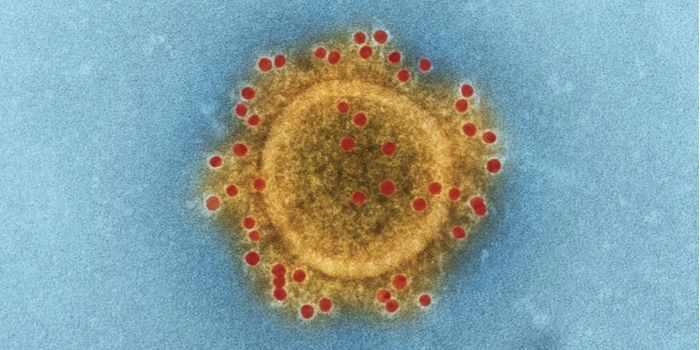

MAR 18, 2020MicrobiologySARS-CoV-2 is a coronavirus that causes an illness called COVID-19. There are now well over 210,000 confirmed cases worl ...